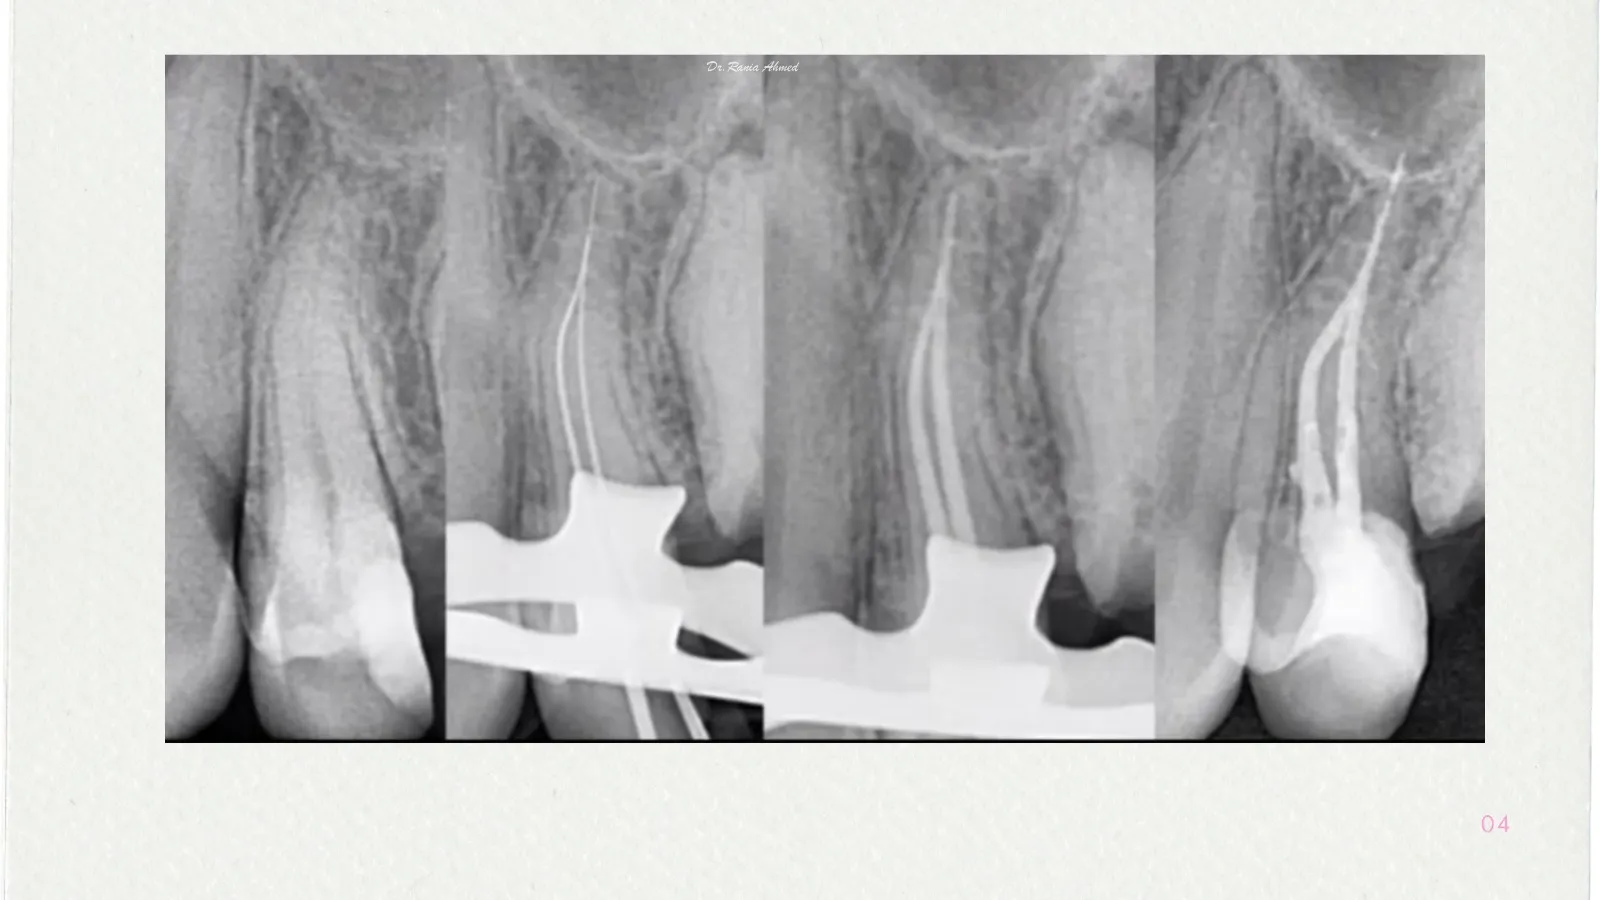

Endodontic Treatment